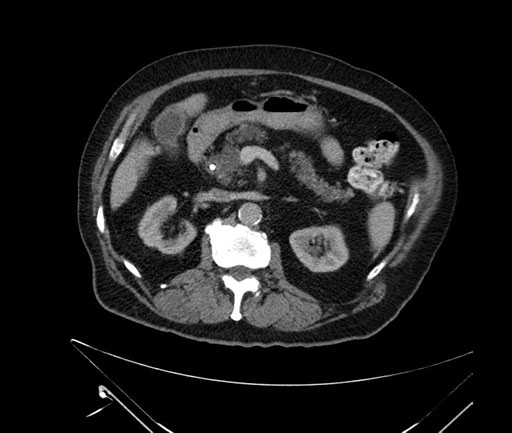

Imaging Analysis

Look through the patient's CT scan to identify any areas of concern for the necessary procedure.

Based on your CT findings, which issue(s) would give reason for "planned slowing down moment(s)" in this case?